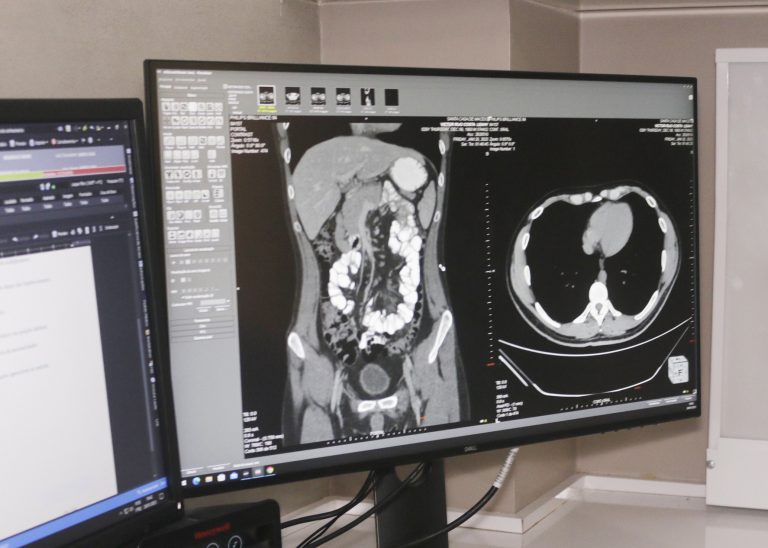

💥 CONTRASTE IÔNICO (TC)

- À base de iodo, usado em exames de Tomografia para aumentar a densidade de estruturas anatômicas.

- Radiopaco, aparece branco nas imagens por absorver os raios-X.